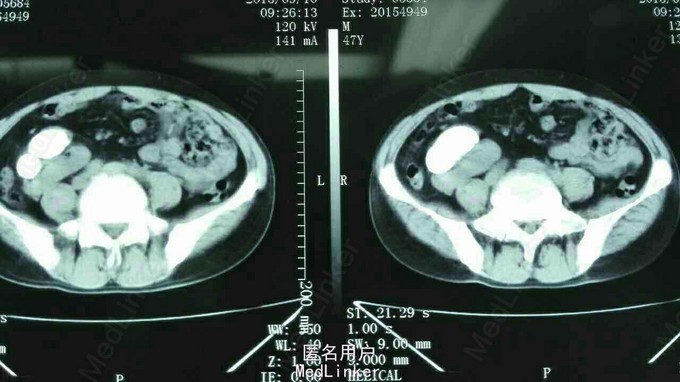

异位肾结石

因反复右侧腹部疼痛5年入院。 5年无诱因出现右侧腹部疼痛,呈阵发性胀痛,无发热,无恶心、呕吐,无尿频、尿急,无肉眼血尿,大便正常,体重无明化。

腹平软,全腹无明显压痛及反跳痛,肠鸣正常,肾区无隆起无叩痛。 辅查,肾功能、血生化均正常。

诊断:右侧异位肾结石并肾积水。 拟行经皮肾镜碎石取石术,但因庙小,患者要求上级医院治疗。